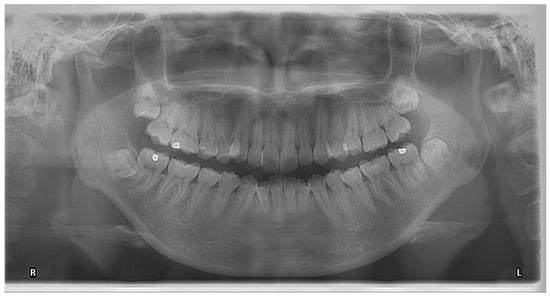

Orthopantomogram (OPG) has been the most useful imaging for the assessment of IAN injury risk of lower third molar surgery [15,16]. OPG is a panoramic scanning dental radiograph that shows a flattened 2D view from one side of the jaw to the other side. Apart from showing the mandible and the maxilla, it also shows the maxillary sinuses, the nasal cavity and the orbits, and for this reason, its applications cover almost all scopes of dentistry [17,18,19,20,21]. OPG is relatively cheap and easily available, with good imaging quality, in particular, at the region around the posterior mandible [22]. The risk of IAN injury is directly related to the proximity of the IAC and the lower third molar root. IAC is a corticated bony canal that harbours the IAN [23]. The understanding of this specific anatomical structure is twofold: (1) The two white lines on the OPG that represent the IAC are formed by the upper and lower cortices of the bony canal since the x-ray is absorbed by the denser bone; (2) The proximity of the third molar root to the IAC will show specific radiographic signs because the canal cortex is bleached or deviated from its course [24,25]. It has been a topic of interest to identify specific radiographic signs of OPG. “Darkening of the root” as a radiographic sign on OPG was consistently found to be related to IAN injury and IAN exposure after third molar removal [24,25,26,27,28] (Figure 1). Leung and Cheung evaluated 178 OPGs with lower third molars showing one or more radiographic signs that indicated close proximity to the IAC and found “darkening of root” and “displacement of the IAC by the root were significantly related to IAN exposure, but only “darkening of root” showed a significant risk of IAN injury. The group also found two or more radiographic signs also showed an increased risk of IAN injury [24]. Other radiographic signs also showed an increased risk of IAN injury but with less consistency [26,29]. Su et al. concluded in their systematic review and meta-analysis that specific radiographic signs of OPG could be considered sufficient for ruling out the risk of postoperative IAN injury but not for ruling out postoperative IAN injury [29]. A meta-analysis by Liu et al. also concurred with the view and concluded despite the interpretation of OPG on “darkening of root” had high specificity in predicting IAN injury after lower third molar surgery, its ability to detect true positive IAN injury was not satisfactory [30].

Figure 1.

OPG showing the darkening of the root of a right lower third molar.